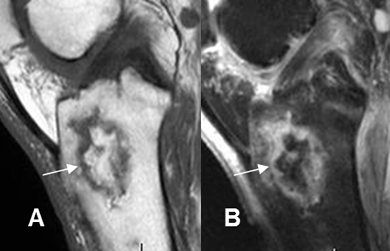

Fig 43 B. Osteomielitis crónica.

A: RM sagital en T1 y B: RM sagital en STIR. Región de hueso “sano” en el tercio proximal de la tibia, rodeado por tejido inflamatorio y que corresponde a secuestro.